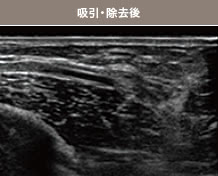

- エコーで確認しながらしこりを除去

ヒアルロン酸ならヒアルロニダーゼ、アクアフィリングなら生理食塩水を注入してしこりを溶かし、乳腺用エコーで確認しながら、注射器で吸引除去します。強い炎症でしこりが瘢痕化(はんこんか:過剰分泌されたコラーゲンが沈着)している場合は、切開手術を行う場合もありますが、傷跡の位置や大きさには十分配慮し、目立たないように工夫して手術を行うのでご安心ください。 -

的確にしこりへ穿刺・注入

しこりの消失を確認

目視することで確実に除去

豊胸の修正手術は、術前から術後まで必ずエコーを実施

術前は、シリコンバッグやしこりの状態を確認します。他院修正の場合は、触診ではわからない症状やバスト内の状態を確認したうえで、傷やダメージをできるだけ抑えられる除去方法を検討。ヒアルロン酸やアクアフィリング除去の場合は、術中もエコーを使用し、目視しながら的確にしこりを除去します。術後は、しこりが完全に除去できたか、同時に脂肪注入した場合は脂肪がしっかり定着しているかのチェックです。術後の仕上がりとゲストの健康状態に責任を持つために、入念なエコー検査を行っています。